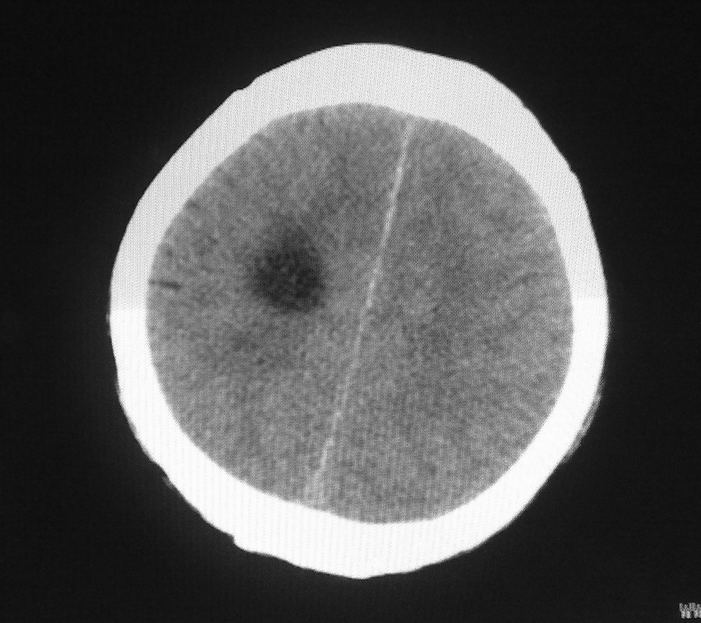

标题: CT24862:男,61岁,发热,有脑出血病史。 [打印本页]

男,61岁,发热,有脑出血病史。

脑积水!四脑室显示不清,导水管梗阻?建议mri!

右侧基底节及放射冠软化灶,脑积水,四脑室显示不清,导水管梗阻?建议mri!

梗阻性脑积水,出血后粘连所致

1)右侧基底节区、右侧放射冠及右侧丘脑软化灶。2)脑积水。